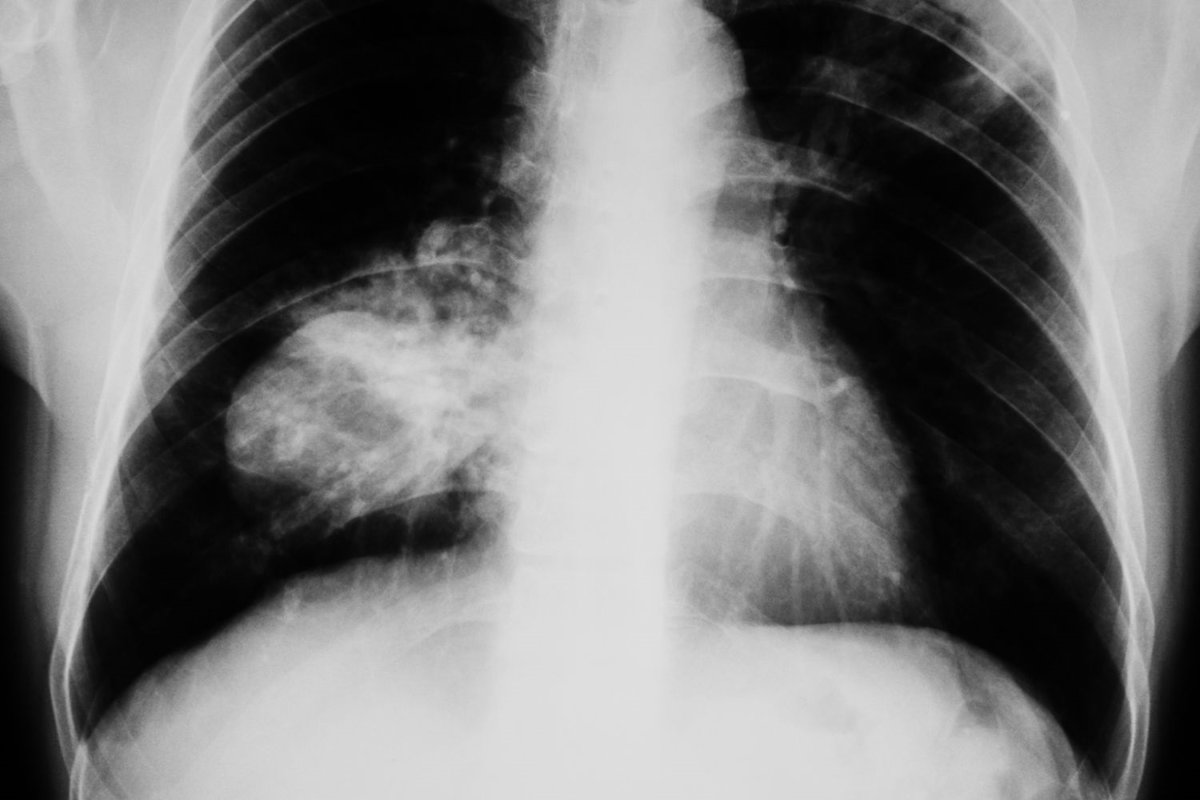

La atención al cáncer de pulmón de célula pequeña (CPCP) en mujeres es un reto global de primer orden, al tratarse de unas de las formas más agresivas de cáncer de pulmón, que afecta al 15% de los diagnósticos y registra una creciente incidencia en mujeres en los últimos años.